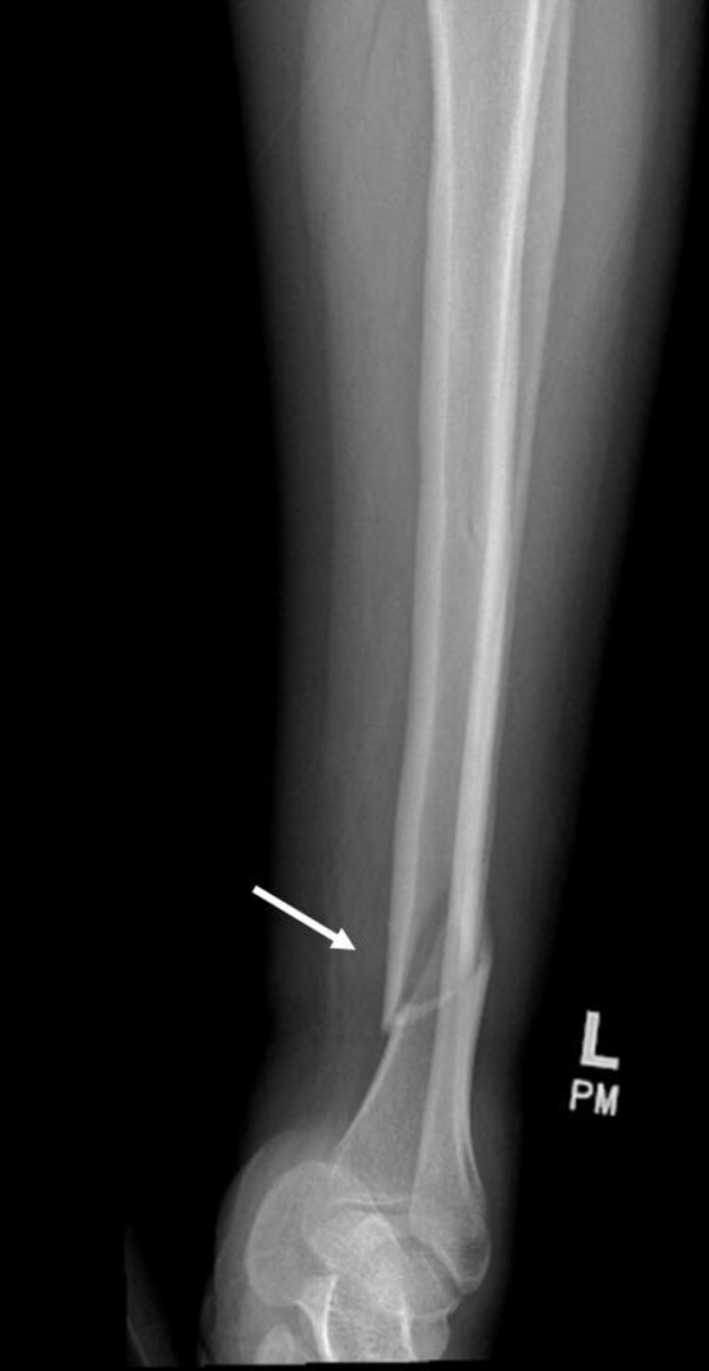

新发完全性心脏传导阻滞(CHB)发生在一个健康的年轻女性是一个相对罕见的发现。我们报告一个病例33岁的女性谁是偶然发现有慢性乙型肝炎后提出了左侧胫骨轴骨折后跌倒。尽管既往有癫痫病史,但长期无癫痫发作,再加上没有神经肌肉无力,这促使我们进行了彻底的调查,最终确定CHB的病因是抗癫痫药物拉科沙胺(LCM)。LCM的停止导致自发性转化为窦性心律,出院后4周的门诊随访显示没有再发生跌倒、心脏传导阻滞或其他症状。我们认为这是一个罕见的lcm诱导的CHB在一个健康的年轻女性。

New-onset complete heart block (CHB) occurring in a healthy young female is a relatively rare finding. We report a case of a 33-year-old female who was incidentally found to have CHB after presenting with a left tibial shaft fracture after a fall. Despite a past medical history of epilepsy, the maintenance of a long, seizure-free period coupled with the absence of neuromuscular weakness prompted a thorough investigation, and the etiology of the CHB was ultimately determined to be lacosamide (LCM), the antiseizure medication. The discontinuation of LCM resulted in spontaneous conversion to sinus rhythm, and an outpatient follow-up 4 weeks after discharge revealed no further episodes of falls, heart block, or other symptoms. We believe this is a rare presentation of LCM-induced CHB in an otherwise healthy young female.